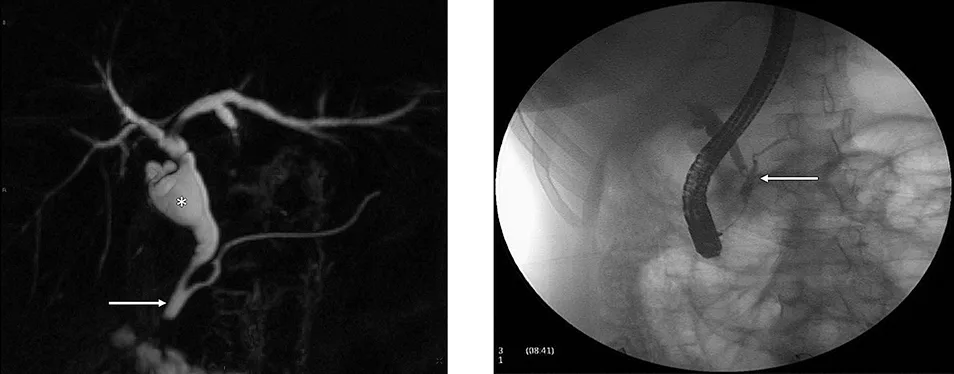

Figure 4 : Aspect en cholangio-IRM des principales variations anatomiques des voies biliaires : trifurcation biliaire (A) ; convergence biliaire étagée avec abouchement direct du canal hépatique antérieur droit (flèche) dans le cholédoque (B) ; canal de Luschka (flèche) compliqué de biliome (étoile) (C) ; gros cholédoque (D)

- Le canal de « Luschka » ou canal biliaire sous-vésiculaire, est un canal biliaire aberrant naissant en dehors du parenchyme hépatique, le plus souvent dans l’espace périvésiculaire, et se drainant dans un canal biliaire intra-hépatique, majoritairement du foie droit.

Ces variations anatomiques sont généralement asymptomatiques mais exposent au risque, en cas de cholécystectomie ou de chirurgie hépatique, de plaie biliaire ou de fuite biliaire dans le cas du canal de « Luschka » (figure 4C). La cholangio-IRM pré-opératoire permet le plus souvent de repérer ces variations et de prévenir une éventuelle complication chirurgicale. Cependant, il n’existe pas de donnée justifiant la réalisation systématique d’une cholangio-IRM avant chirurgie vésiculaire, et celle-ci n’est donc pas recommandée.